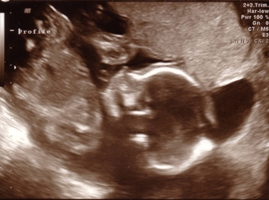

Sono pics... can i see your 20 week ones?

Okay so i went yesterday for my 20 week sono and my pictures S*CK!!!! I don't understand how some of you have such great pictures and mine have been awful!

your sono is cute!!! Your baby is showing us his/her butt!

Awe Ali, he/she is so cute!! Look at that coolie! you can see the spine, so awesome!! you'll get better ones. can you go back and ask for more?

oh its cute... I see the spine!

Aaaww I think it's cute how you can see the spine so clearly and how your baby is looking down with his/her little butt up!!!!